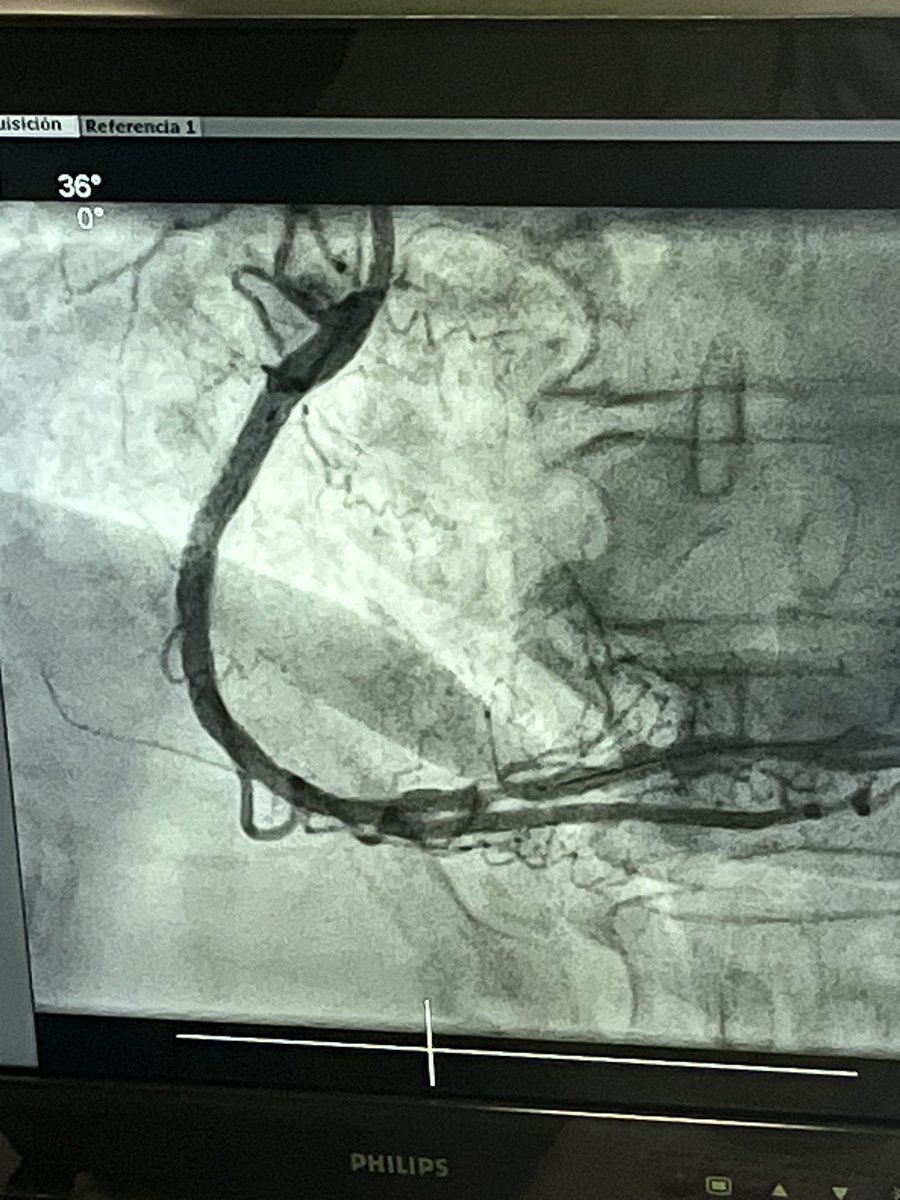

Seguimos con el curso TACTICaL del Hospital del Mar Magnífico caso de ICP de CTO muy compleja del Dr. José Montero Euro4cSpain ACI-SEC: Hemodinamica Soc Esp Cardiología #EAPCI #Euro4C #CTO #CHIP Beatriz @helenatmCARDIO Rut Álvarez Velasco Jorge Palazuelos josep